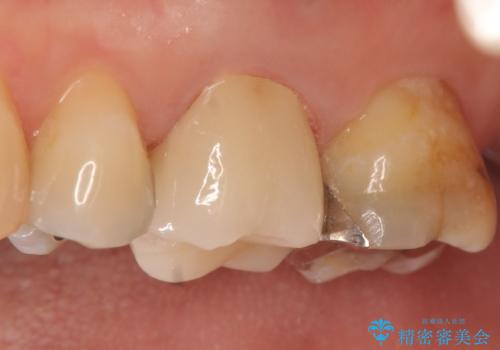

フィステルの消失を確認後、オールセラミッククラウンによる補綴を行いました。

今回用いたオールセラミッククラウンはジルコニアフレームという白い素材の上にセラミックを盛っているため、審美性が非常に高いのが特徴です。

また、ジルコニアは人工ダイヤモンドの材料にも使われているほど高い強度を持っており、そのためオールセラミッククラウンは審美性だけでなく、奥歯やブリッジの補綴も可能とするクラウンです。